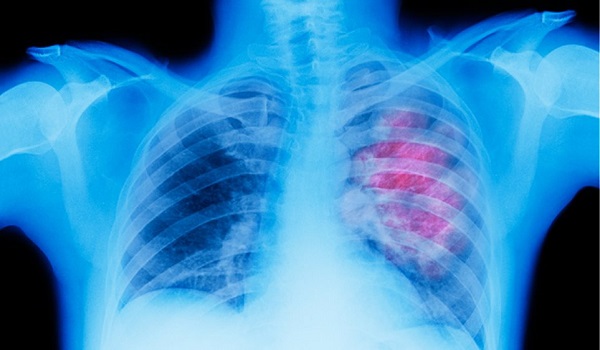

Ο μικροκυτταρικός καρκίνος του πνεύμονα χαρακτηρίζεται από την παρουσία κυττάρων από καρκινικούς όγκους στους ιστούς των πνευμόνων.

Ο μικροκυτταρικός καρκίνος του πνεύμονα αντιπροσωπεύει το 10-15% όλων των περιπτώσεων καρκίνου του πνεύμονα και τυπικά περιλαμβάνει ταχέως αναπτυσσόμενους, επιθετικούς όγκους. Το κάπνισμα είναι ο πιο κοινός παράγοντας κινδύνου που συνδέεται slot gacor με αυτή την μορφή καρκίνου.

Υπάρχουν δύο κύριες μορφές καρκίνου του πνεύμονα: μικροκυτταρικός και μη-μικροκυτταρικός. Ο δεύτερος είναι πολύ πιο συχνός και έχει καλύτερη προοπτική ίασης από τον πρώτο.

Τα καρκινικά κύτταρα που σχετίζονται με τον μικροκυτταρικό situs judi slot terbaik dan terpercaya no 1 καρκίνο του πνεύμονα τείνουν να είναι μικρότερα και οι όγκοι αναπτύσσονται σχετικά γρήγορα, γεγονός που κάνει την έγκαιρη ανίχνευση και διάγνωσή του δύσκολη.